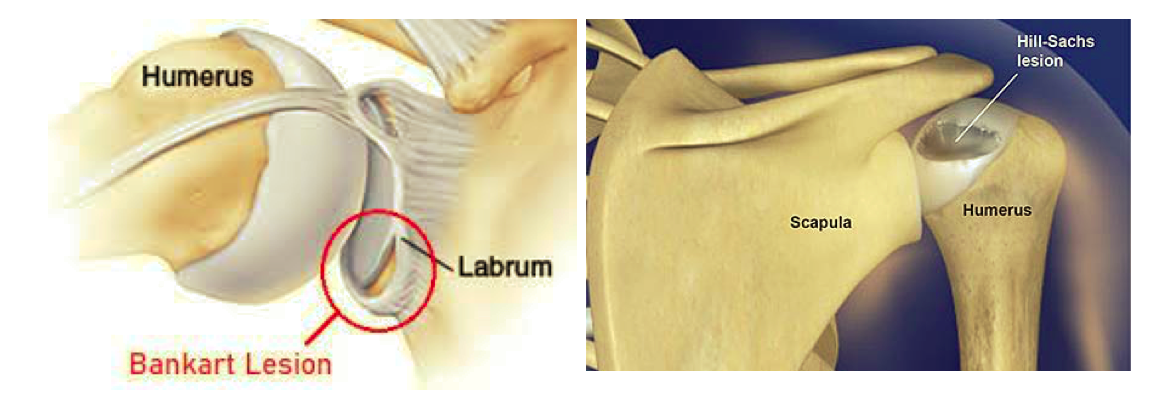

What are some associated injuries with shoulder dislocation? (2 things)

- Bony Bankart lesion = detachment of ant. labrum from glenoid

- Hill Sachs = osteochondral depression #